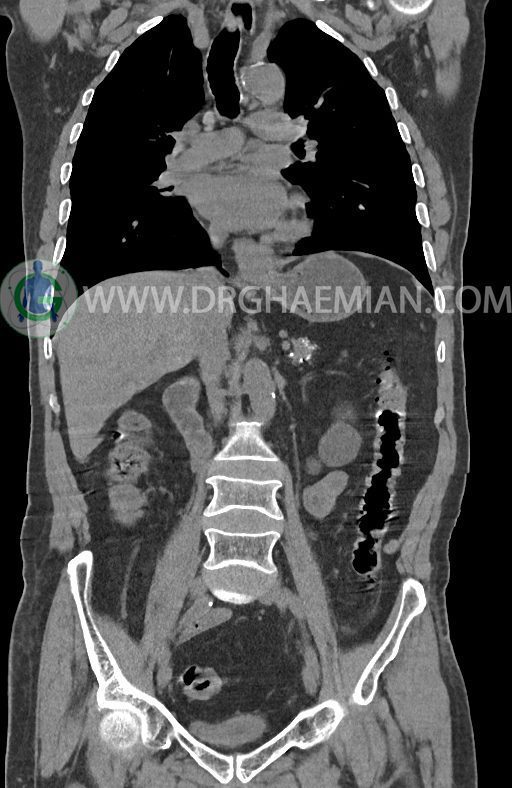

در سی تی اسکن اسپیرال ریه ها و مدیاستن، شکم و لگن با و بدون کنتراست وریدی (مولتی دیدکتور 16 با مقاطع ظریف و بازسازی کرونال) :

–افزایش ضخامت تومورال دیستال مری و GEJ در سگمانی به طول 4cm-5cm (T2 or T3)

-3 لنف نود رژیونال با SAD ≤ 9 mm دیده می شود. (N2)

–آتروفی نسبی پانکراس همراه با فوکوس های کلسیفیه ی منتشر پارانشیم مطرح کننده ی پانکراتیت مزمن

-CBD بسیار دیلاته (16mm) همراه با دیلاتاسیون مجاری داخل کبدی سنترال بدون شواهد سنگ یا توده در مسیر

–کیست های کورتیکال متعدد هر دو کلیه به بزرگترین قطر 56mm

نتیجه : T(2or3)/N2/M0